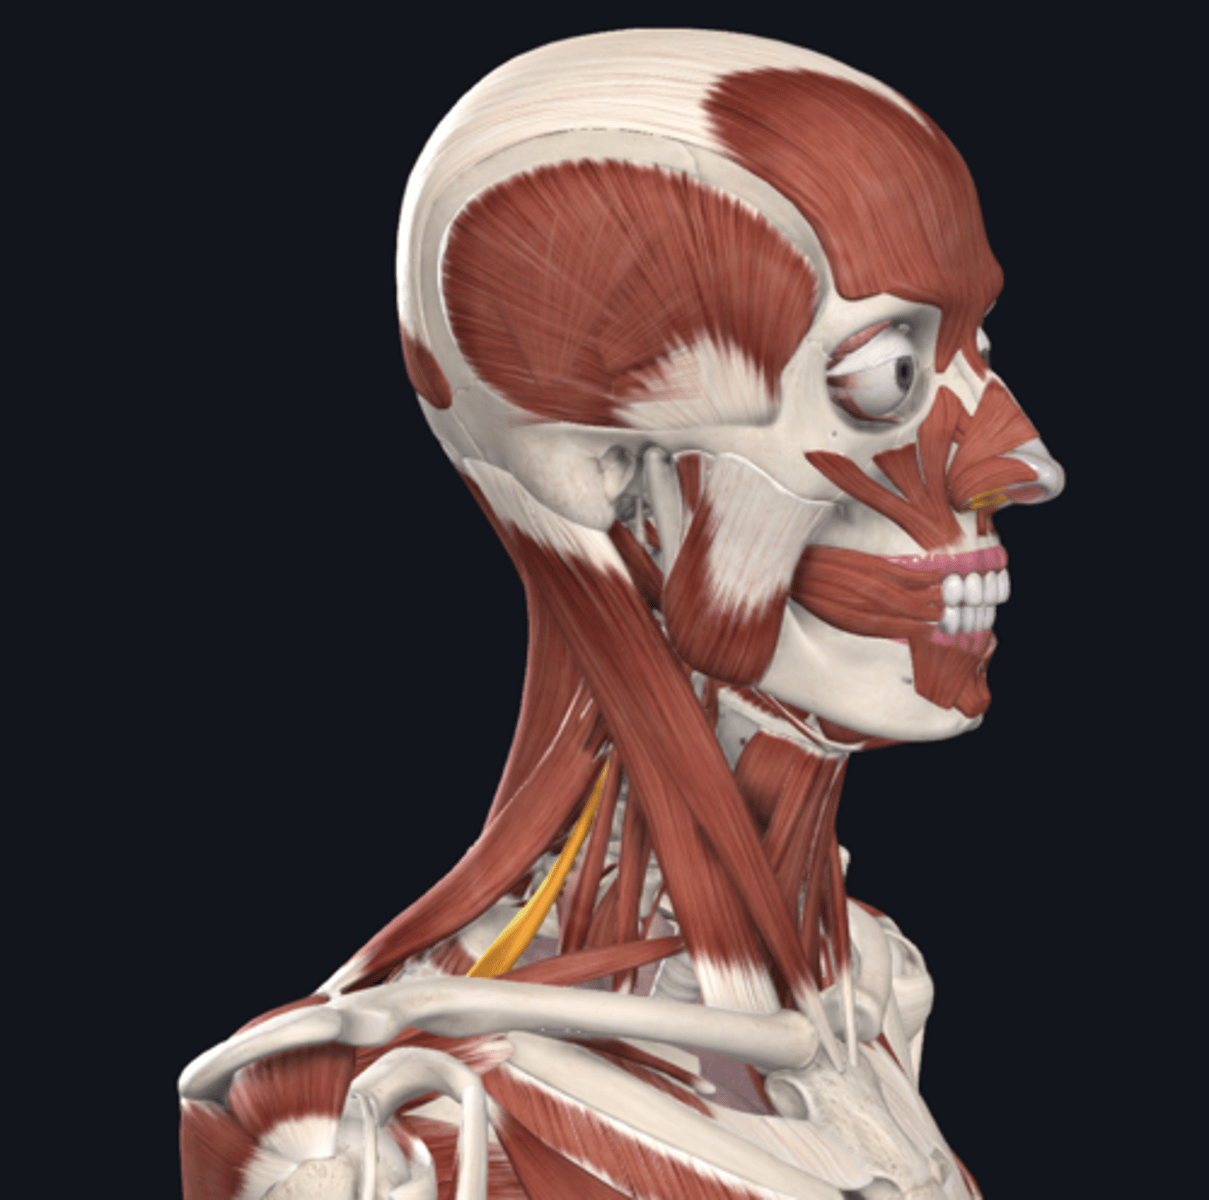

anterior scalene

middle scalene

posterior scalene

sternocleidomastoid

scalene muscles (surface anatomy)

name these muscles

thyroid cartilage (surface anatomy)

Adam's apple

trachea (surface anatomy)

feel for trachial cartilages